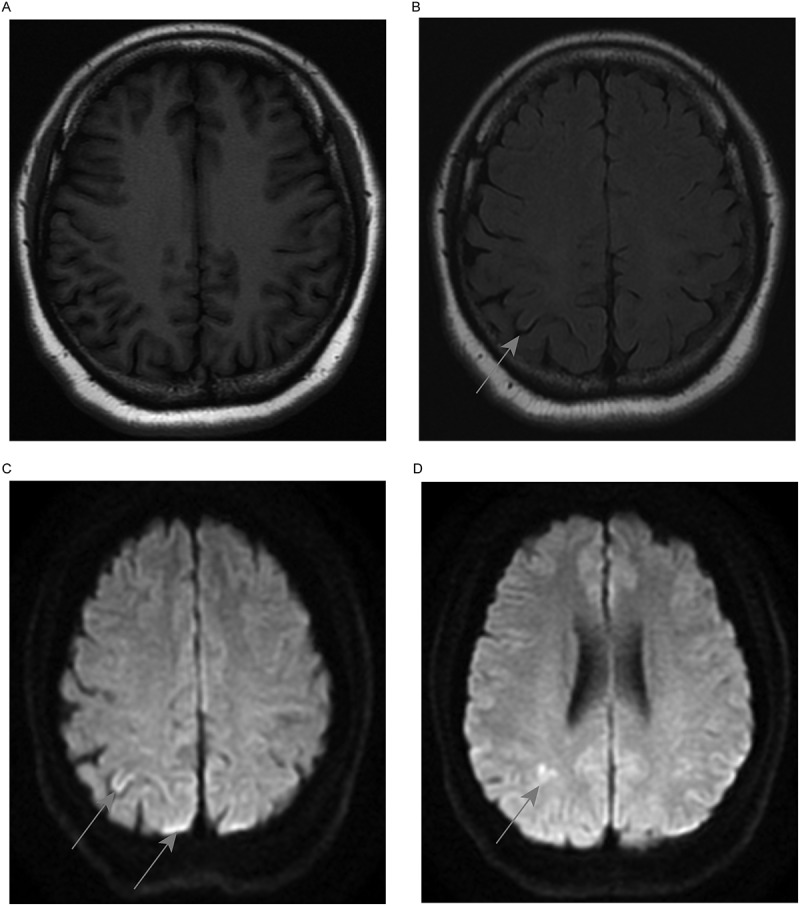

Gerstmann Sträussler Scheinker(GSS)病是一种常染色体显性遗传的神经退行性疾病,以进行性小脑共济失调为特征。到目前为止,具有p.P102L突变的GSS病例主要在高加索人中报道,但在亚洲人群中很少报道。一名54岁的女性患者在医院里步态不稳。去年,她无法稳定行走,偶尔会哽咽,甚至逐渐无法独立行走。在记录了她的病史后,我们发现她在步态问题之前被误诊为精神分裂症。患者的父亲表现出类似的症状,在56岁时被诊断为脑萎缩,但她的女儿目前没有表现出类似症状。到达神经内科后,患者的生命体征和实验室检查均无异常。由于先证者表现为小脑共济失调,并且有明显的家族史,我们确信她患有遗传性小脑共济失调。然后,患者的大脑MRI显示右顶叶皮层有异常信号,额叶有双侧小缺血病变。进行基因分析(包括142个共济失调相关基因),并鉴定出一个杂合突变PRNP Exon2 c.305C>T p.(Pro102Leu)。她的女儿也有同样的杂合突变。该患者被诊断为GSS,最初症状为精神障碍。经过2个月的中医治疗,患者的行走不稳定性下降,情绪波动也比以前小。总之,我们在中国四川报告了一例罕见的GSS病例,以精神障碍为首发症状的家庭最终被确认为GSS PRNP P102L突变。

Gerstmann-Sträussler-Scheinker (GSS) disease is an autosomal dominant neurodegenerative disease, and it is characterized by progressive cerebellar ataxia. Up to now, GSS cases with the p.P102L mutation have mainly been reported in Caucasian, but rarely in Asian populations. A 54-year-old female patient presented with an unstable gait in the hospital. Last year, she was unable to walk steadily and occasionally choked, could not even walk independently gradually. After taking her medical history, we found that she was misdiagnosed with schizophrenia before the gait problems. The patient's father showed similar symptoms and was diagnosed with brain atrophy at the age of 56, but her daughter showed no similar symptoms at present. On arrival at the Neurology Department, the patient's vital signs and laboratory examinations showed no abnormality. As the proband presented with cerebellar ataxia and had an obvious family history, we were sure that she had hereditary cerebellar ataxia. Then, patient's brain MRI showed an abnormal signal in the right parietal cortex and bilateral small ischaemic lesions in the frontal lobe. A gene panel (including 142 ataxia-related genes) was performed, and a heterozygous mutation PRNP Exon2 c.305C>T p. (Pro102Leu) was identified. Her daughter had the same heterozygous mutation. The patient was diagnosed with GSS with mental disorders as initial symptoms. After 2 months of TCM treatment, the patient's walking instability decreased, and her emotional fluctuations were less than before. In conclusion, we have reported a rare case of GSS in Sichuan, China, and the family with mental disorder as the first symptom was finally confirmed with GSS PRNP P102L mutation.